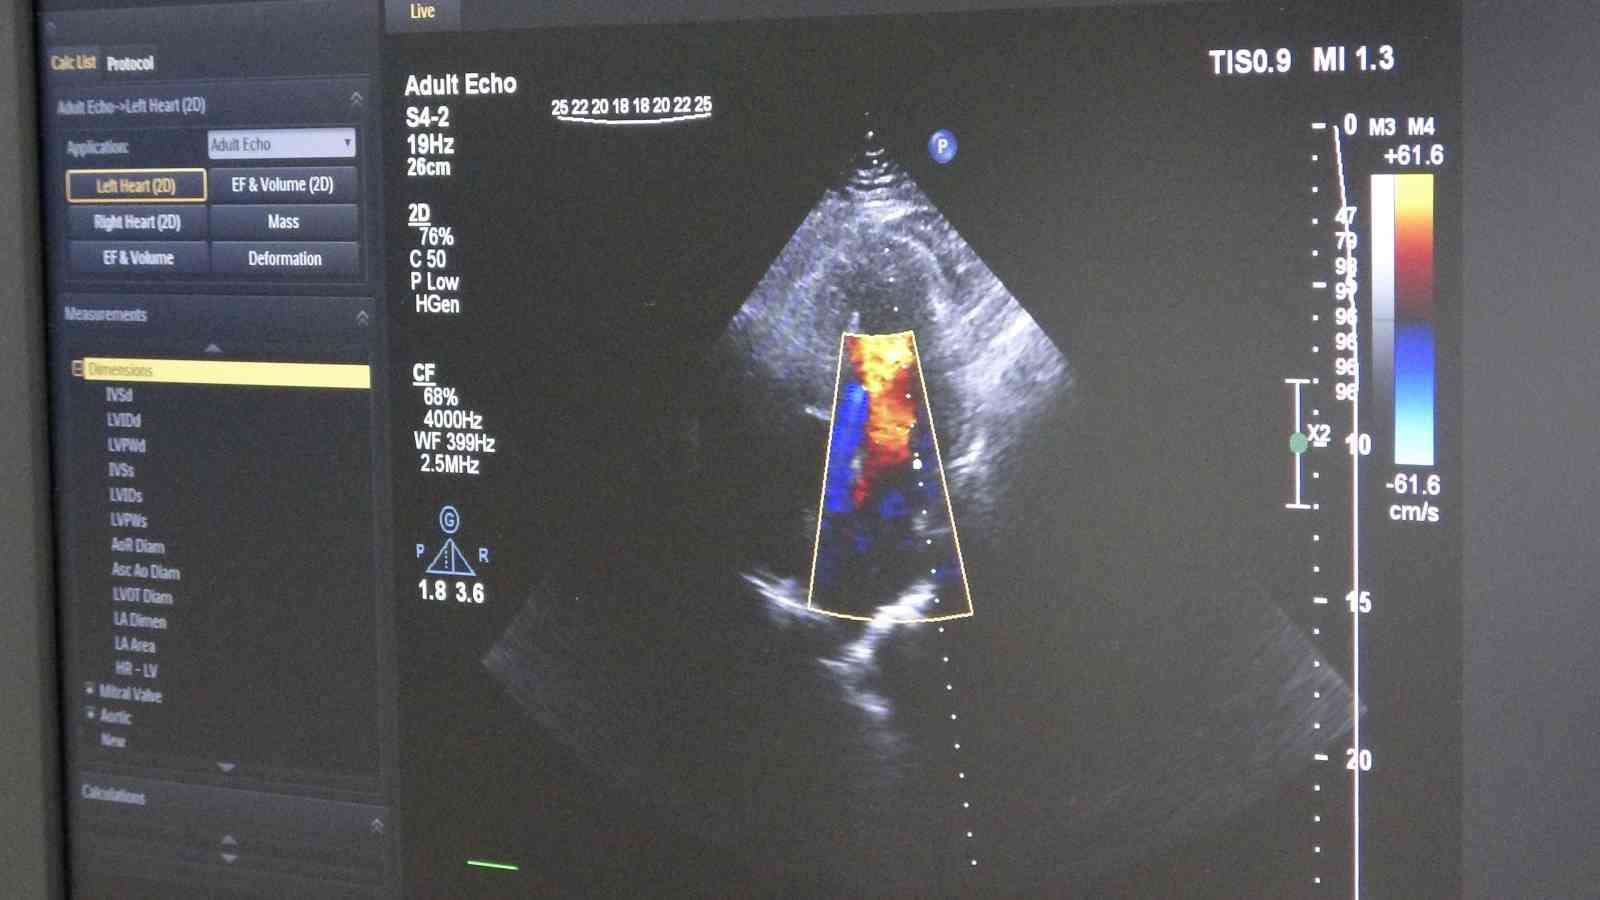

Gelişen teknolojiyle birlikte öne çıkan tedavi yöntemlerinden biri olan ilaç kaplı balon uygulaması, damara kalıcı metal yapı bırakmadan tedavi imkânı sunuyor. Bu yöntemde, özel ilaç kaplı balon damar içerisinde genişletilerek hem darlık gideriliyor hem de ilaç doğrudan damar duvarına etki ediyor.

Tedavi sürecinde damar yapısının ayrıntılı incelendiğini belirten Dereli, "İşlem öncesinde intravasküler ultrason (IVUS) ile damar duvarını değerlendiriyoruz. Ayrıca fraksiyonel akım rezervi (FFR) ile darlığın kan akımına etkisini ölçüyoruz. Bu yöntemler, doğru karar vermemizi ve başarılı sonuç elde etmemizi sağlıyor" diye konuştu.